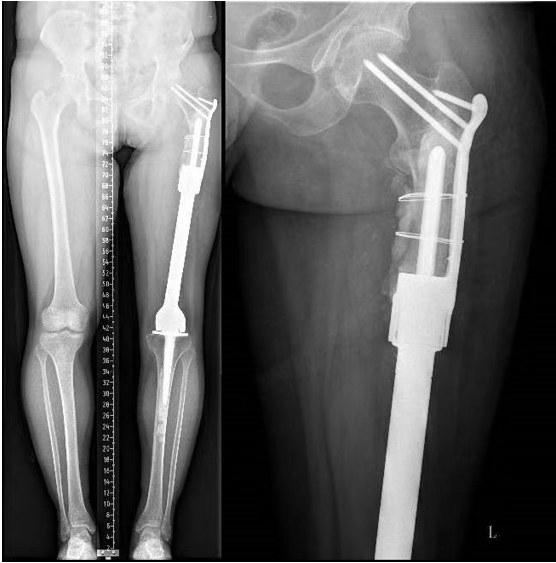

术后效果达到预期,患者很快便可以自理,恢复了肢体长度,且疼痛消失。黄先生出院后送来锦旗,感谢常黎明副院长及廖光军主任的手术团队,给他来了新的希望和更高质量的生活。

术后影像资料